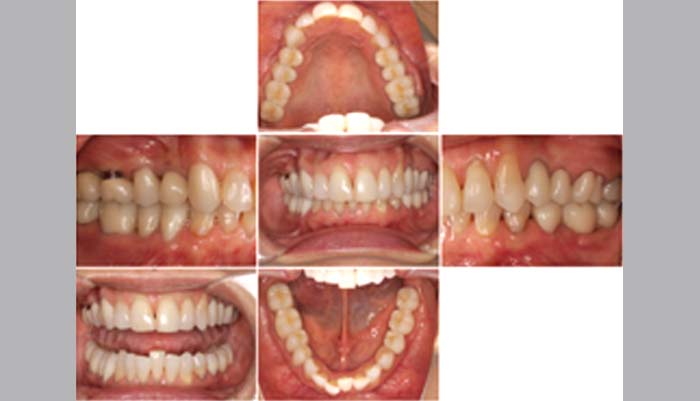

治療後